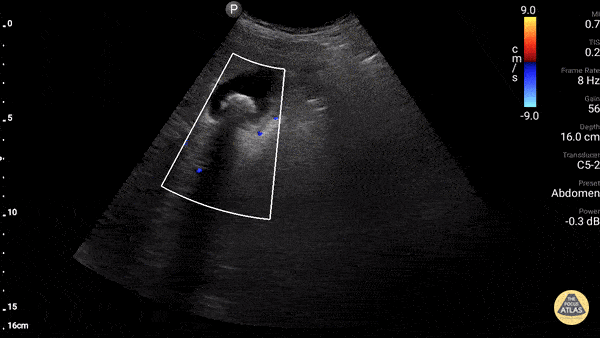

Gallbladder with non-obstructing stone. Fanning down one sees the portal triad with bile duct (black) 7 mm, hepatic artery (pulsitile) and portal vein (red). Dr. Gordon Johnson